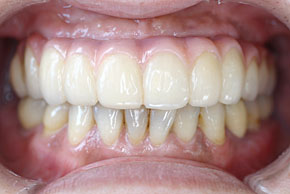

インプラントと周りの歯肉が安定したところで形をとって、最終のインプラント義歯を装着します。

ほとんど自分の歯と見分けがつかない程度にきれいになります。もちろん口蓋の部分には義歯はなく、歯だけですので違和感はほとんどありません。患者様には例外なく喜んでいただいています。このインプラント義歯は取り外しできるため、当科で1年に1度外して、きれいにします。

料金はかかる費用をほぼすべて加算し、上下とも各220万円程度です。